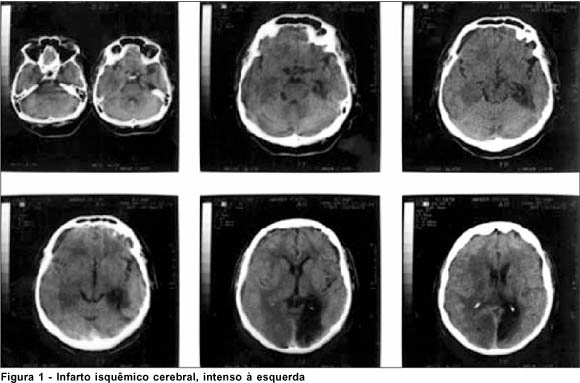

Em 09/01/99, V.S.S., masculino, 65 anos, queixava perda súbita da visão bilateral há quatro dias. Relatava visão prévia normal e negava episódio similar anterior. Tabagista há 20 anos e hipertenso com mal controle clínico, negava uso de medicação e negava também diabetes mellitus ou outras patologias. Ao exame clínico a sua visão era de percepção luminosa no olho esquerdo e ausência de percepção luminosa no olho direito. Em ambos os olhos a biomicroscopia estava normal, a pressão intra-ocular encontrava-se em seu limite superior (20mmHg) e os reflexos pupilares estavam ligeiramente diminuídos. À fundoscopia notava-se oclusão venosa da arcada temporal no olho direito e ausência de alterações no olho esquerdo. A tomografia computadorizada (11/01/99) revelou área hipodensa occipital bilateral, infartos seqüelares occipitais bilaterais e ateromatose bicarotideana. A arteriografia apresentou (Figuras 2 A e B) ateroma na carótida interna direita, aterosclerose difusa em todo encéfalo (bilateralmente), obstruções arteriais significativas e placas ateromatosas em todo trajeto basilar. O paciente foi acompanhado por um ano e apresentou melhora da acuidade visual para percepção luminosa no olho direito e manteve a percepção luminosa no olho esquerdo.

No caso 1, a presença de um êmbolo de origem cardíaca pode ter tido importância no aparecimento do evento isquêmico cerebral. A embolização é uma causa freqüente de obstrução da circulação retiniana e êmbolos cardíacos ou carotídeos são os mais comuns(7-8). A oftalmoscopia binocular indireta não mostrou sinais que justificassem a ausência de percepção luminosa bilateral. O campo visual neste caso foi inviável pela ausência de percepção de luz. A tomografia computadorizada de crânio (Figura 1) auxiliou o diagnóstico ao revelar área de infarto isquêmico cerebral em ambos os hemisférios. A alteração fundoscópica no segundo caso (oclusão venosa da arcada temporal em olho direito) poderia dificultar o diagnóstico, entretanto foi detectada somente no olho direito enquanto que a perda visual foi bilateral. Tais achados fundoscópicos poderiam, provavelmente, ter surgido antes da cegueira cortical ou concomitantes, uma vez que tanto a oclusão venosa da retina quanto a cegueira cortical bilateral possuem como principais fatores de risco hipertensão arterial sistêmica e doenças cardiovasculares(7). A tomografia computadorizada de crânio revelou infartos seqüelares occipitais bilaterais e ateromatose bicarotideana. Neste caso também havia alterações vasculares e isquêmicas à arteriografia (Figuras 2A e B). Em ambos os casos os pacientes apresentaram diminuição da acuidade visual, reflexos pupilares praticamente normais e ausência de alterações na oftalmoscopia binocular indireta. Tal quadro e os achados tomográficos caracterizaram o diagnóstico(9). O acompanhamento subseqüente dos pacientes foi realizado simultaneamente por neurologista, cardiologista e oftalmologista. O primeiro caso foi acompanhado pelo oftalmologista por 8 meses e, atualmente, faz controle ambulatorial. Não ocorreu melhora da acuidade visual em nenhum dos olhos. O segundo paciente foi submetido, no Departamento de Retina, a fotocoagulação da oclusão de ramo venoso em olho direito e encontra-se em controle ambulatorial. Apresentou melhora da acuidade visual para percepção luminosa no olho direito e manteve percepção luminosa no olho esquerdo, depois de 1 ano de seguimento. De acordo com a literatura médica, o prognóstico da cegueira cortical é reservado, mas em alguns casos pode haver o retorno gradual da visão até percepção luminosa e de movimentos de mãos (9). Normalmente o prognóstico depende de causa, gravidade, duração da doença e melhoria inicial rápida do quadro(5). Aldrich e colaboradores em 1987 observaram que em 15 pacientes com cegueira cortical o melhor prognóstico foi observado naqueles com menos de 40 anos, sem fatores de risco, como hipertensão arterial sistêmica e diabetes mellitus, e sem alterações cognitivas, de linguagem ou de memória(9). Nos presentes casos, a acuidade visual não melhorou, a não ser no segundo caso, no qual ocorreu leve melhora da percepção luminosa em olho direito. Levando em conta que ambos tinham mais de 40 anos de idade, hipertensão arterial e um deles também diabetes mellitus, pode-se dizer que a evolução e o quadro clínico de ambos estão de acordo com os dados observados na literatura(10). Cuellar & Sanchez também relataram uma melhora da acuidade visual em poucos dias de evolução, em pacientes jovens com cegueira cortical pós-operatória(11).